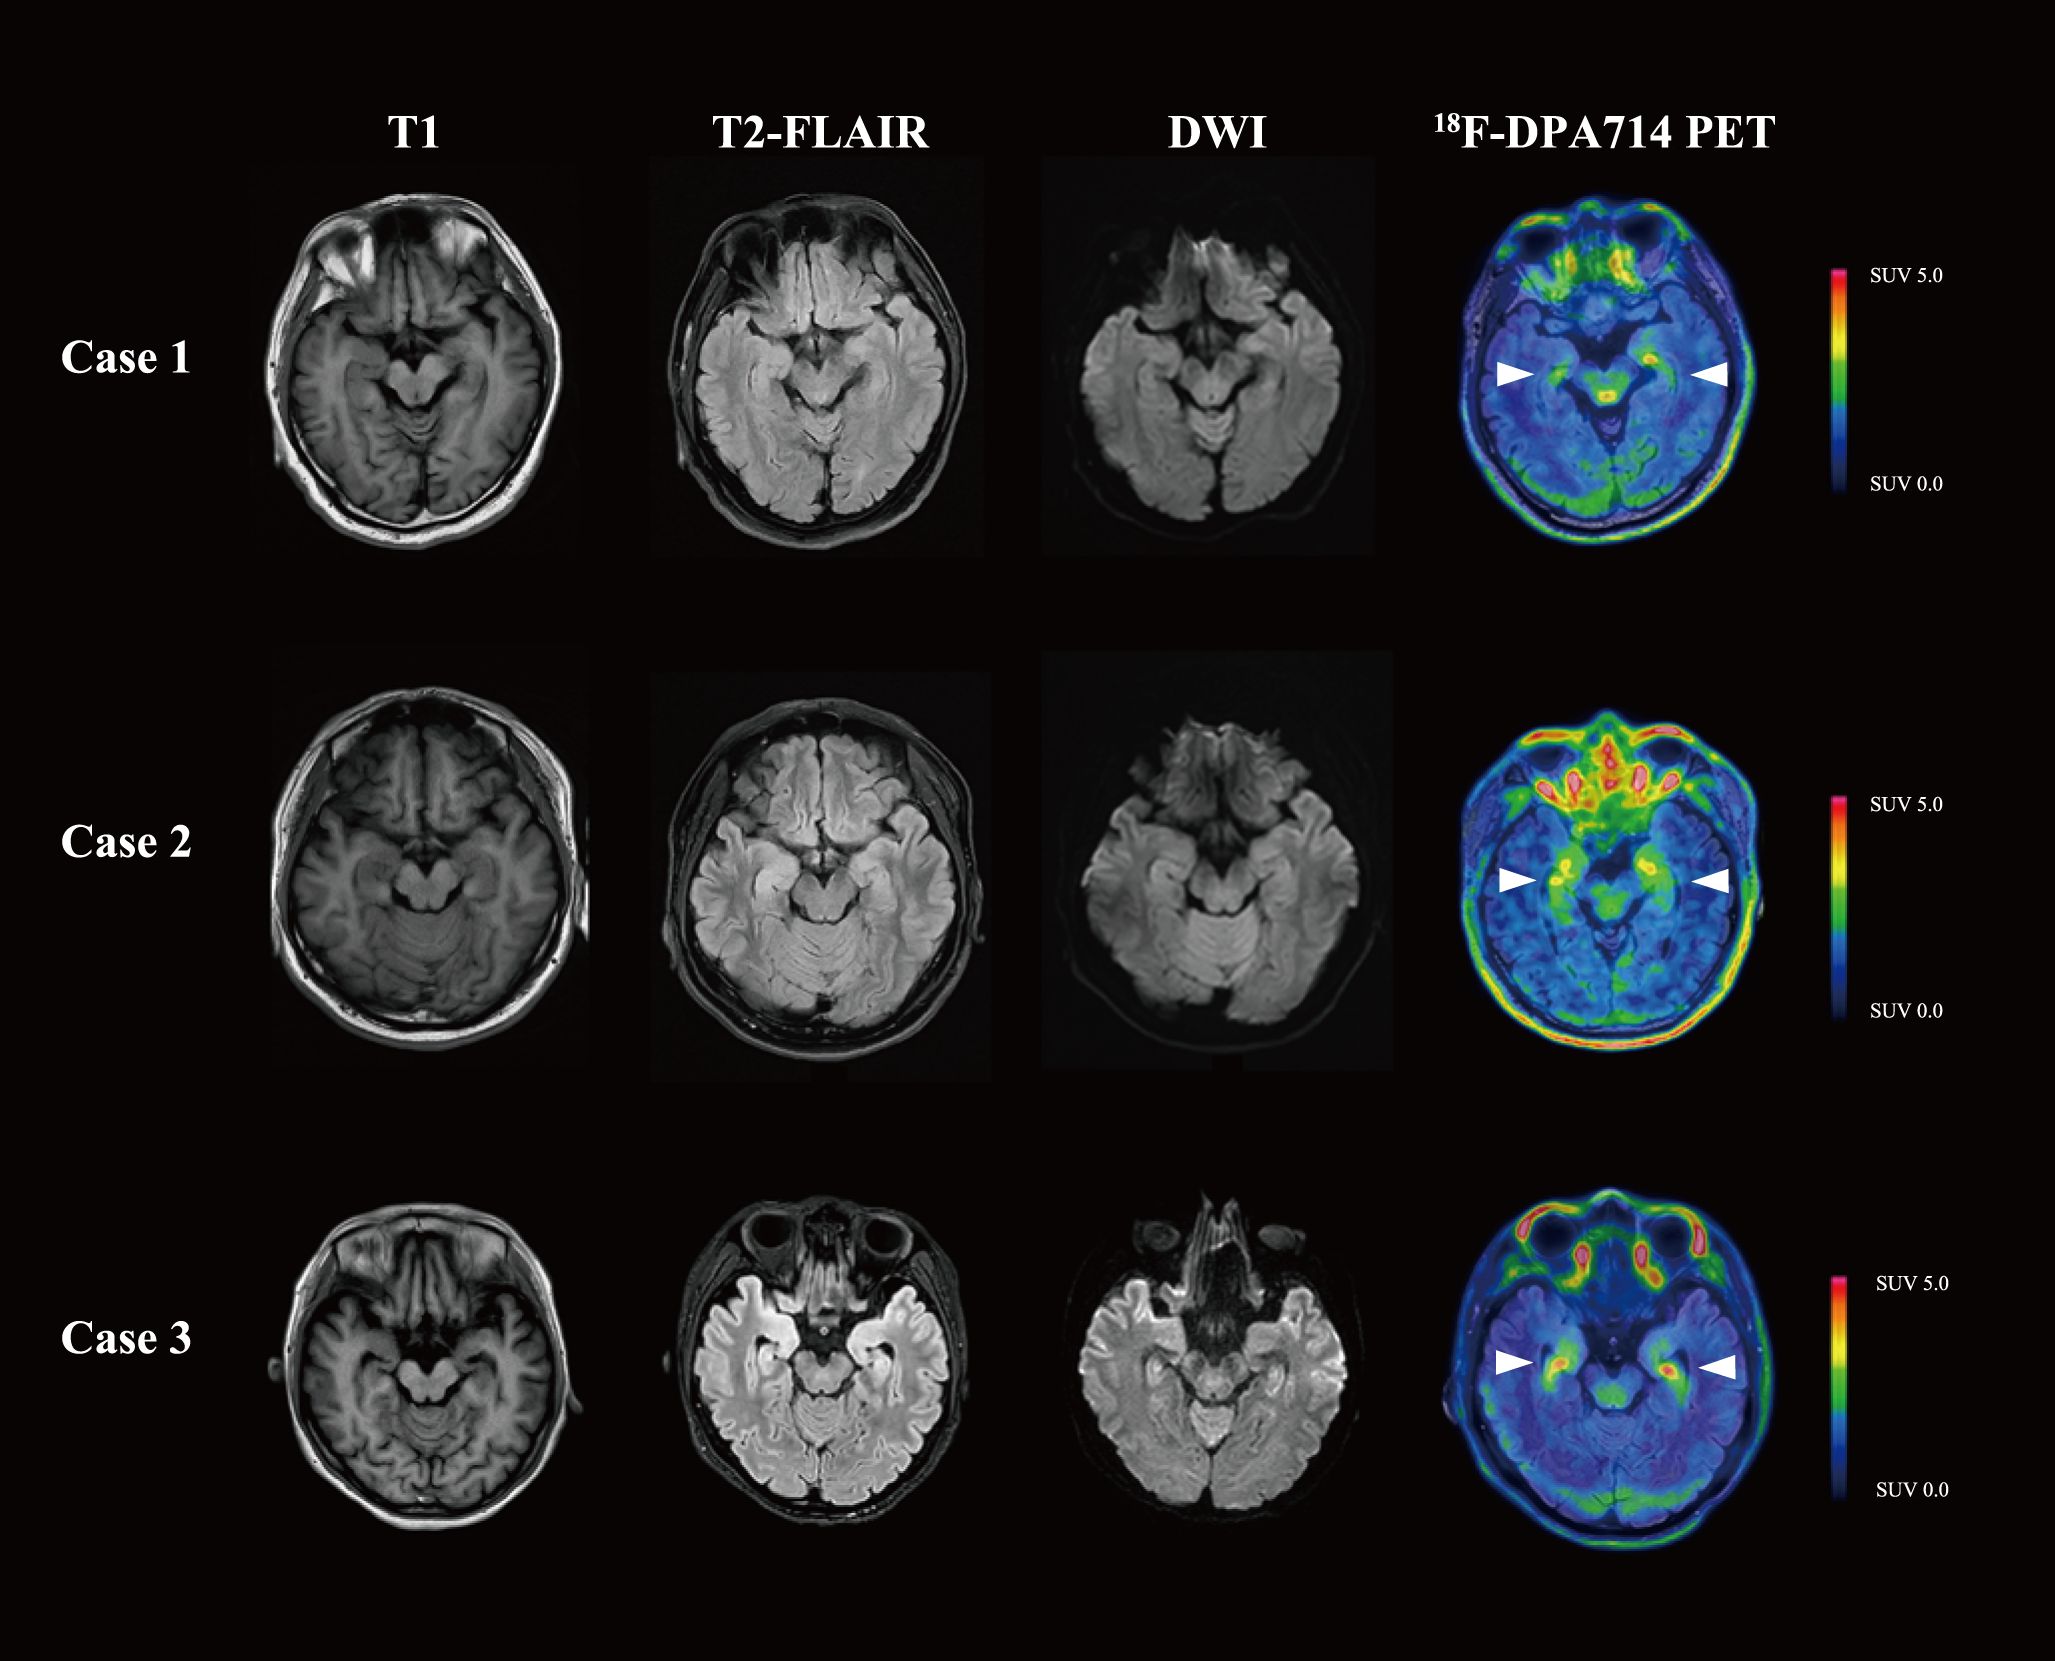

The fourth disease episode developed 3 months after the previous relapse. Upon readmission for evaluation, neurological evaluation demonstrated aggravated cognitive deficit and memory impairment, with mRS score of 2, CASE score of 4, and MMSE score of 17. Anti-NMDAR antibody was constantly positive in serum (titer 1:100). However, the laboratory tests revealed normal serum IgG (7.89 g/L) and IgM (0.51 g/L), as well as a depleted level of CD20+ B cell (0%) and CD19+ B cell (0.1%). While cranial magnetic resonance imaging (MRI) revealed no significant abnormalities, 18F-DPA714 PET/MRI imaging demonstrated elevated tracer uptake in the bilateral medial temporal lobes (Figure 1) (11). Given the patient’s history of multiple relapses and treatment-refractory disease, along with comorbid conditions, telitacicept (160 mg per two weeks for 12 weeks) was added to the ongoing regimen of oral prednisone (5 mg once daily) and MMF (0.25 g twice daily). Laboratory monitoring conducted 3 months after telitacicept initiation revealed a slight decline in serum immunoglobulins (IgG 6.2 g/L, IgM 0.40 g/L) concomitant with serological anti-NMDAR antibody reduction (titer 1:10). Clinical improvement became perceptible one month after telitacicept initiation and was evidenced by affective stabilization and cognitive enhancement, with an mRS score of 1, a CASE score of 2 and an MMSE score of 24. Longitudinal monitoring over 6 months demonstrated sustained therapeutic efficacy, with neurological function preservation reflected in both stable mRS and CASE assessment at 1. No disease flares or treatment-emergent adverse events were documented during this period.

Figure 1. Brain MRI and 18F-DPA714 PET/MRI images of the three patients. Cases 1 and 2 presented with normal MRI, while Case 3 was found to have T2-FLAIR and DWI hyperintensity in the bilateral medial temporal lobes. In 18F-DPA714 PET/MRI, all three patients had elevated uptake in the bilateral medial temporal lobes. T1, T1-weighted imaging; T2-FLAIR, T2-weighted fluid attenuated inversion recovery; DWI, diffusion weighted imaging.

A 42-year-old man presented with progressive memory deficits over one month, accompanied by left upper–limb myoclonic jerks. On admission, neurological examination revealed speech disfluency and short-term memory impairment, with an mRS score of 2, CASE score of 5, and an MMSE score of 20. CSF analysis revealed normal opening pressure, cell count, proteins, glucose, and chloride levels. AE antibodies test (CBA, Simcere Diagnosis, Nanjing, China) indicated anti-leucine-rich glioma inactivated 1 (LGI1) antibody was positive in CSF (titer 1:10) and serum (titer 1:1000). Ambulatory electroencephalogram indicated sharp waves in the temporo-centro-occipital area. While Cranial MRI and whole-body 18F-FDG-PET/CT were normal, cranial 18F-DPA714-PET/MRI revealed an elevated neuroinflammation in bilateral medial temporal lobes (Figure 1). Therefore, the patient was diagnosed with anti-LGI1 antibody encephalitis.

A 37-year-old female was admitted for cognitive impairment and myokymia in lower limbs for one month, accompanied by weakness, paresthesia, palpation, and sleep disorder. Physical examination demonstrated impaired arithmetic ability and generalized limbic muscle weakness (muscle strength graded 4-). Functional assessment revealed an mRS score of 3, a CASE score of 4, and an MMSE score of 18. Laboratory studies identified hyponatremia (129 mmol/L). CSF analysis showed normal opening pressure, cell count, proteins, glucose, and chloride levels. Electromyogram showed no abnormalities, yet electroencephalogram depicted mild θ wave activity with individual sharp waves in the left central temporal area. Brain MRI revealed T2-weighted fluid attenuated inversion recovery (T2-FLAIR) and diffusion weighted imaging (DWI) hyperintensity in the right hypothalamus and bilateral medial temporal lobes. 18F-FDG-PET/CT demonstrated hypermetabolism in the right hypothalamus and focally in the left occipital lobe. 18F-DPA714 PET/MRI showed significantly increased uptake in the bilateral medial temporal lobes (Figure 1). The AE-related antibodies panel test (CBA, Simcere Diagnosis, Nanjing, China) confirmed dual positivity for anti-LGI1 antibody (titer CSF 1:30, serum 1:100) and anti-contactin-associated protein 2 (CASPR2) antibody (titer CSF 1:10, serum 1:100).